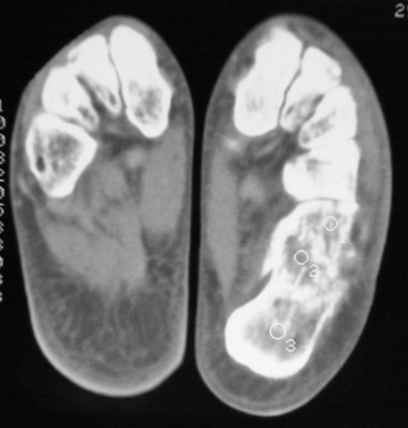

Уважаемые коллеги! Пришел на консультацию больной - "растяжение связок левого голеностопного сустава" полтора месяца назад, поскольку был в морях, на ногу не наступал. Снимки и КТ - в приложении.

Как бы кто лечил с учетом времени после травмы - 52 дня? Человек физического труда. Социальные запросы самого больного высокие, плюс медкомиссии перед рейсами - с хромотой нельзя!